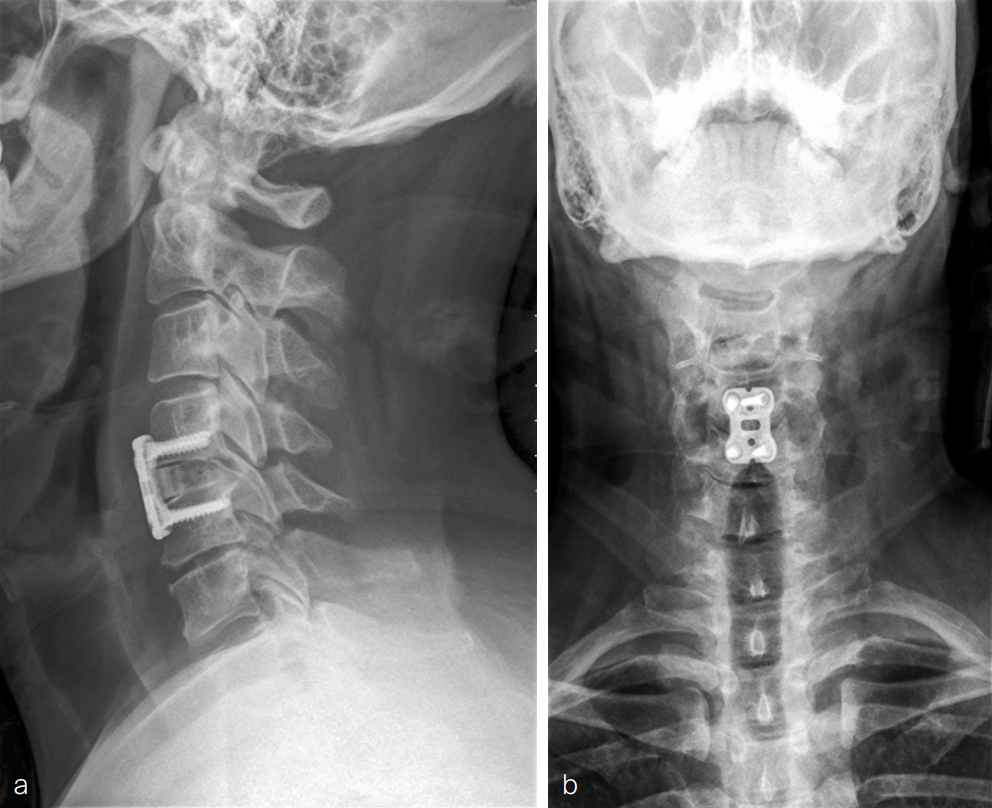

A diagnosis was made of cervical spinal stenosis largely attributable to stenosis at C4/5, with lesser stenosis at C5/6 and cord compression causing sub-acute central cord syndrome. Anterior decompression was recommended to alleviate symptoms, and C4/5 anterior cervical discectomy and fusion (ACDF) was performed on March 7, 2024. Fig 9 shows postoperative imaging.

At 6-month follow-up, muscle strength was greatly improved with physical examination showing 5 out of 5 strength throughout both upper extremities. Sensation was normal in both upper extremities. The patient had a good range of motion in the cervical spine. He continued to have some problems with fatigue whilst handwriting. There was some residual pain and neuropathy bilaterally, in a small area from the mid-forearm to the mid-bicep. The nerve symptoms tended to fluctuate throughout the day. Continued improvement was anticipated with ongoing physical therapy.

Anteroposterior and lateral, flexion, and extension x-rays showed that the graft at C4/5 appeared to be in the original position as expected. There was no evidence of loosening of the screw-plate construct. Some bridging fusion was present between the superior C5 endplate of the graft. There continued to be incomplete consolidation between C4 and the graft but no motion of the graft itself. Flexion/extension films did not show any instability.